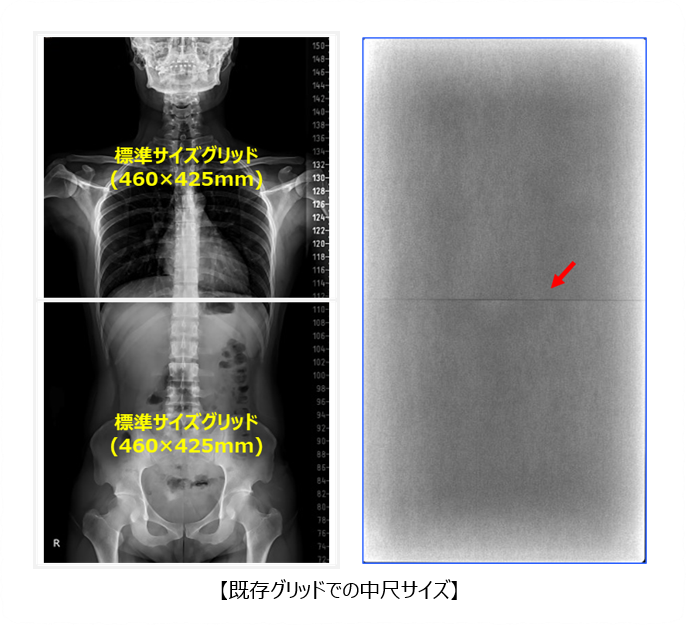

■メガグリッド

従来、長尺・中尺サイズのグリッドは、2~3枚を連結して製造されていました。

そのため、連結部が画像中心付近に位置し、主要な患部が映る中心部と干渉するという課題がありました。

当社では、グリッドの製造可能サイズを最大680×680mmまで拡大する技術を開発し、連結部を任意の位置に配置することで、画像中心部と干渉しないグリッドの製造を実現しています。